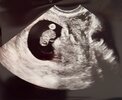

Hehehe rozbraja mnie NuggetsAle Nuggetsowi ładnie serce biło i ma już 1,48 cm

Haha a jakHehehe rozbraja mnie Nuggetstaki już całkiem apetyczny kąsek rzekła bym